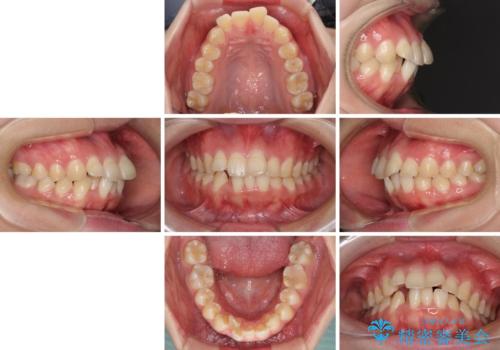

- 上の前歯の出っ歯とでこぼこの歯並びを気にして来院された患者様です。

口元を積極的に引っ込めるために、上下左右の小臼歯4本を抜歯することとしました。